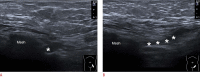

Inguinal hernia is the most prevalent type of abdominal wall hernia. Indirect inguinal hernia is twice as common as direct inguinal hernia. Computed tomography and magnetic resonance imaging can be used to evaluate inguinal hernia, but these modalities are greatly limited by their cost and availability. Ultrasonography has emerged as the most convenient imaging tool for diagnosing inguinal hernia due to its advantages, such as portability and absence of radiation. The present pictorial review presents an overview on the use of ultrasonography in the evaluation of inguinal hernia with a particular emphasis on the regional anatomy, relevant scanning tips, identification of subtypes, postoperative follow-up, and diagnosis of pathologies mimicking inguinal hernia.